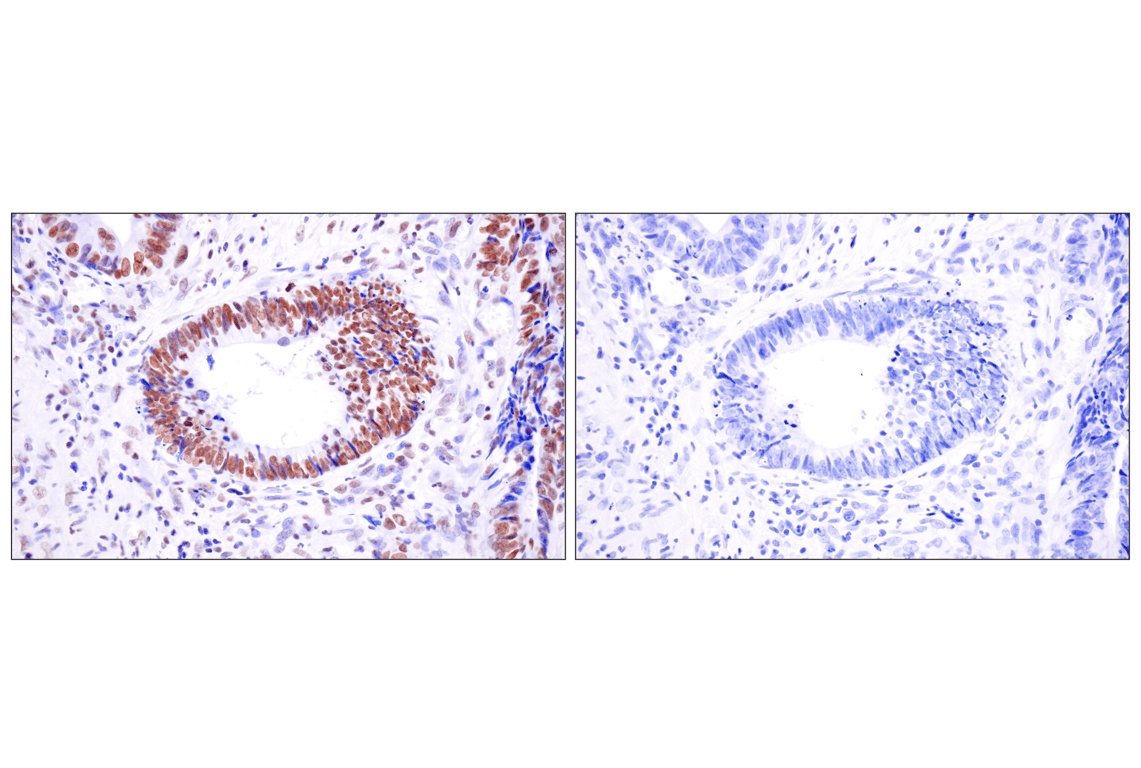

Immunohistochemical analysis of paraffin-embedded human urothelial carcinoma using Acetyl-Histone H4 (Lys16) (E2B8W) Rabbit mAb in the presence of non-acetyl-peptide (left) or K16 acetyl-peptide (right).

Immunohistochemistry Image 8: Acetyl-Histone H4 (Lys16) (E2B8W) Rabbit Monoclonal Antibody